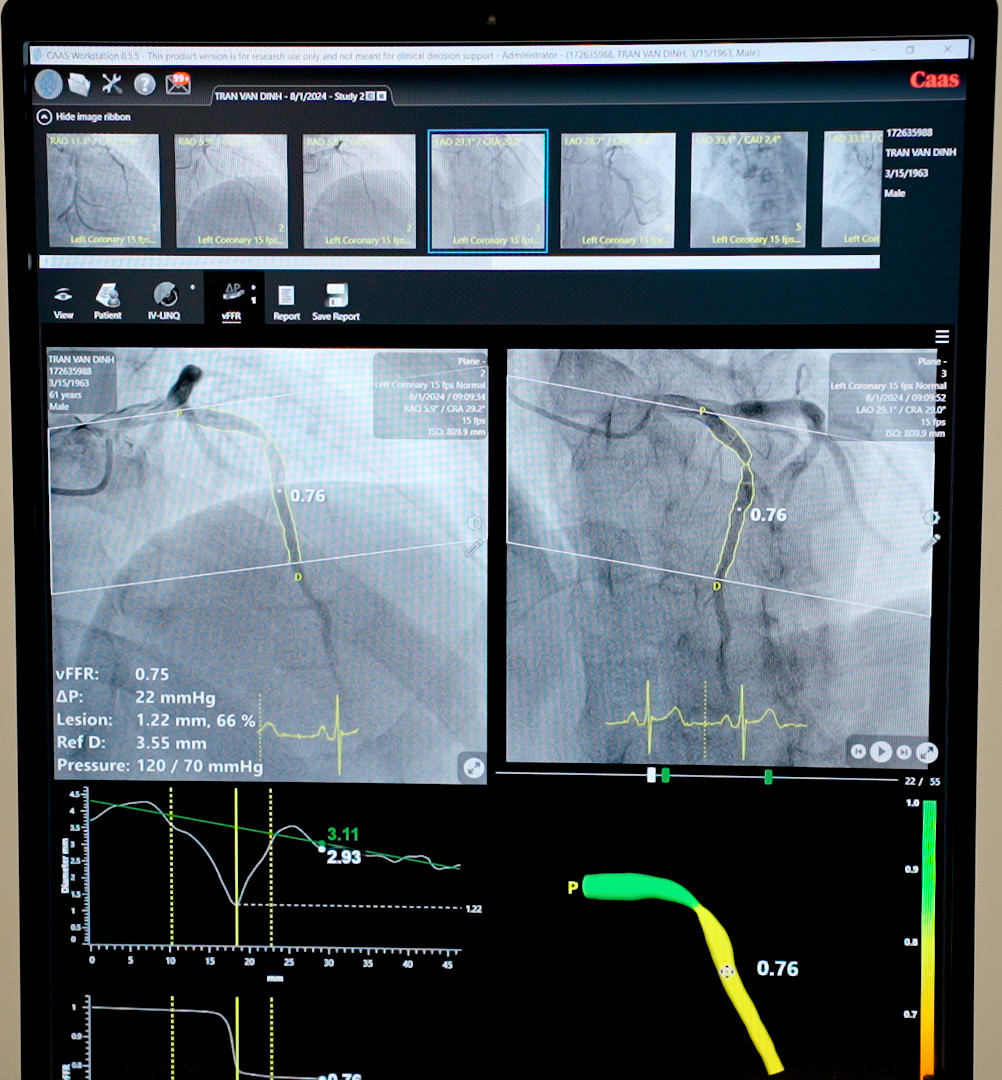

![]() |

| Tình trạng hẹp mạch vành của bệnh nhân được đo trên phần mềm vFFR |

Với việc cung cấp các hình ảnh chụp mạch vành và huyết áp, phần mềm vFFR sẽ tái tạo mô hình 3D của các động mạch này. Sau đó tự động phân tích phân tích lưu lượng dòng máu qua các đoạn hẹp của động mạch vành dưới dạng báo cáo các chỉ số chi tiết để hiển thị trên màn hình. Từ đó giúp bác sĩ có dữ liệu đánh giá đầy đủ, toàn diện để đưa ra phương án điều trị tối ưu nhất.

Theo Ths.Bs Nguyễn Văn Hải - Trưởng Khoa Tim mạch – Tim mạch can thiệp BVĐK Hồng Ngọc, vFFR là kỹ thuật mới, đo phân suất lưu lượng dự trữ vành không xâm lấn với độ chính xác rất cao, thời gian cho kết quả chỉ mất vài phút, giúp bác sĩ tiết kiệm thời gian và kinh phí cho bệnh nhân.